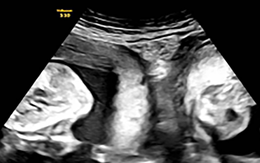

Hy hữu người phụ nữ sinh đôi từ tử cung đôi

Một sản phụ ở Trung Quốc vừa sinh đôi một trai một gái từ hai tử cung khác nhau, một trường hợp cực kỳ hiếm gặp.

Hai bé sinh đôi từ 2 tử cung của mẹ, vào 2 ngày khác nhau

Đây là trường hợp sinh đôi hiếm gặp với tỉ lệ 1/50 triệu phụ nữ mang thai.